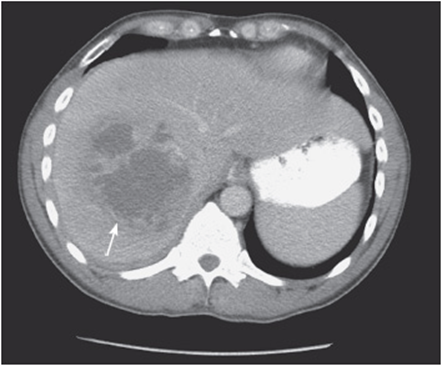

• An intra-abdominal fluid collection could be a benign/malignant tumor or an intra-abdominal abscess (see Figure 56-4).

Figure 56-4. Two intra-abdominal fluid collections, suspicious for abscesses.